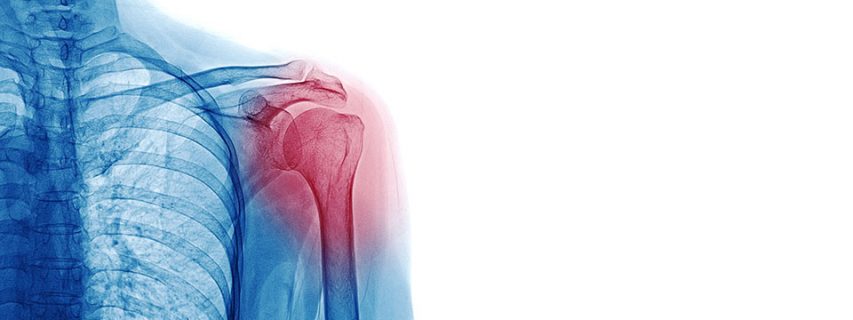

The shoulder labrum is a ring of cartilage that lines and reinforces the ball socket joint of the shoulder. Ligaments are attached to the labrum and it contributes to the overall stability of the shoulder. When the labrum is torn, the shoulder can become partially or completely dislocated.